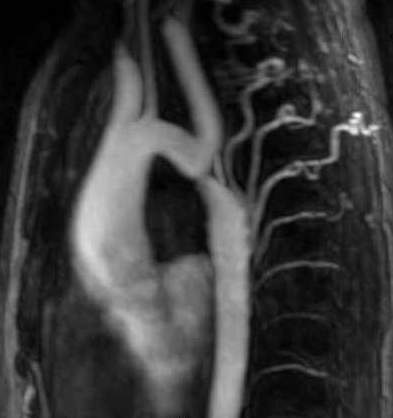

Image

Contrast enhanced MR angiography

Control CT angiography after stent implantation to correct a bilateral arterial stenosis

Fig. 18., 19.: Renal artery stenosis